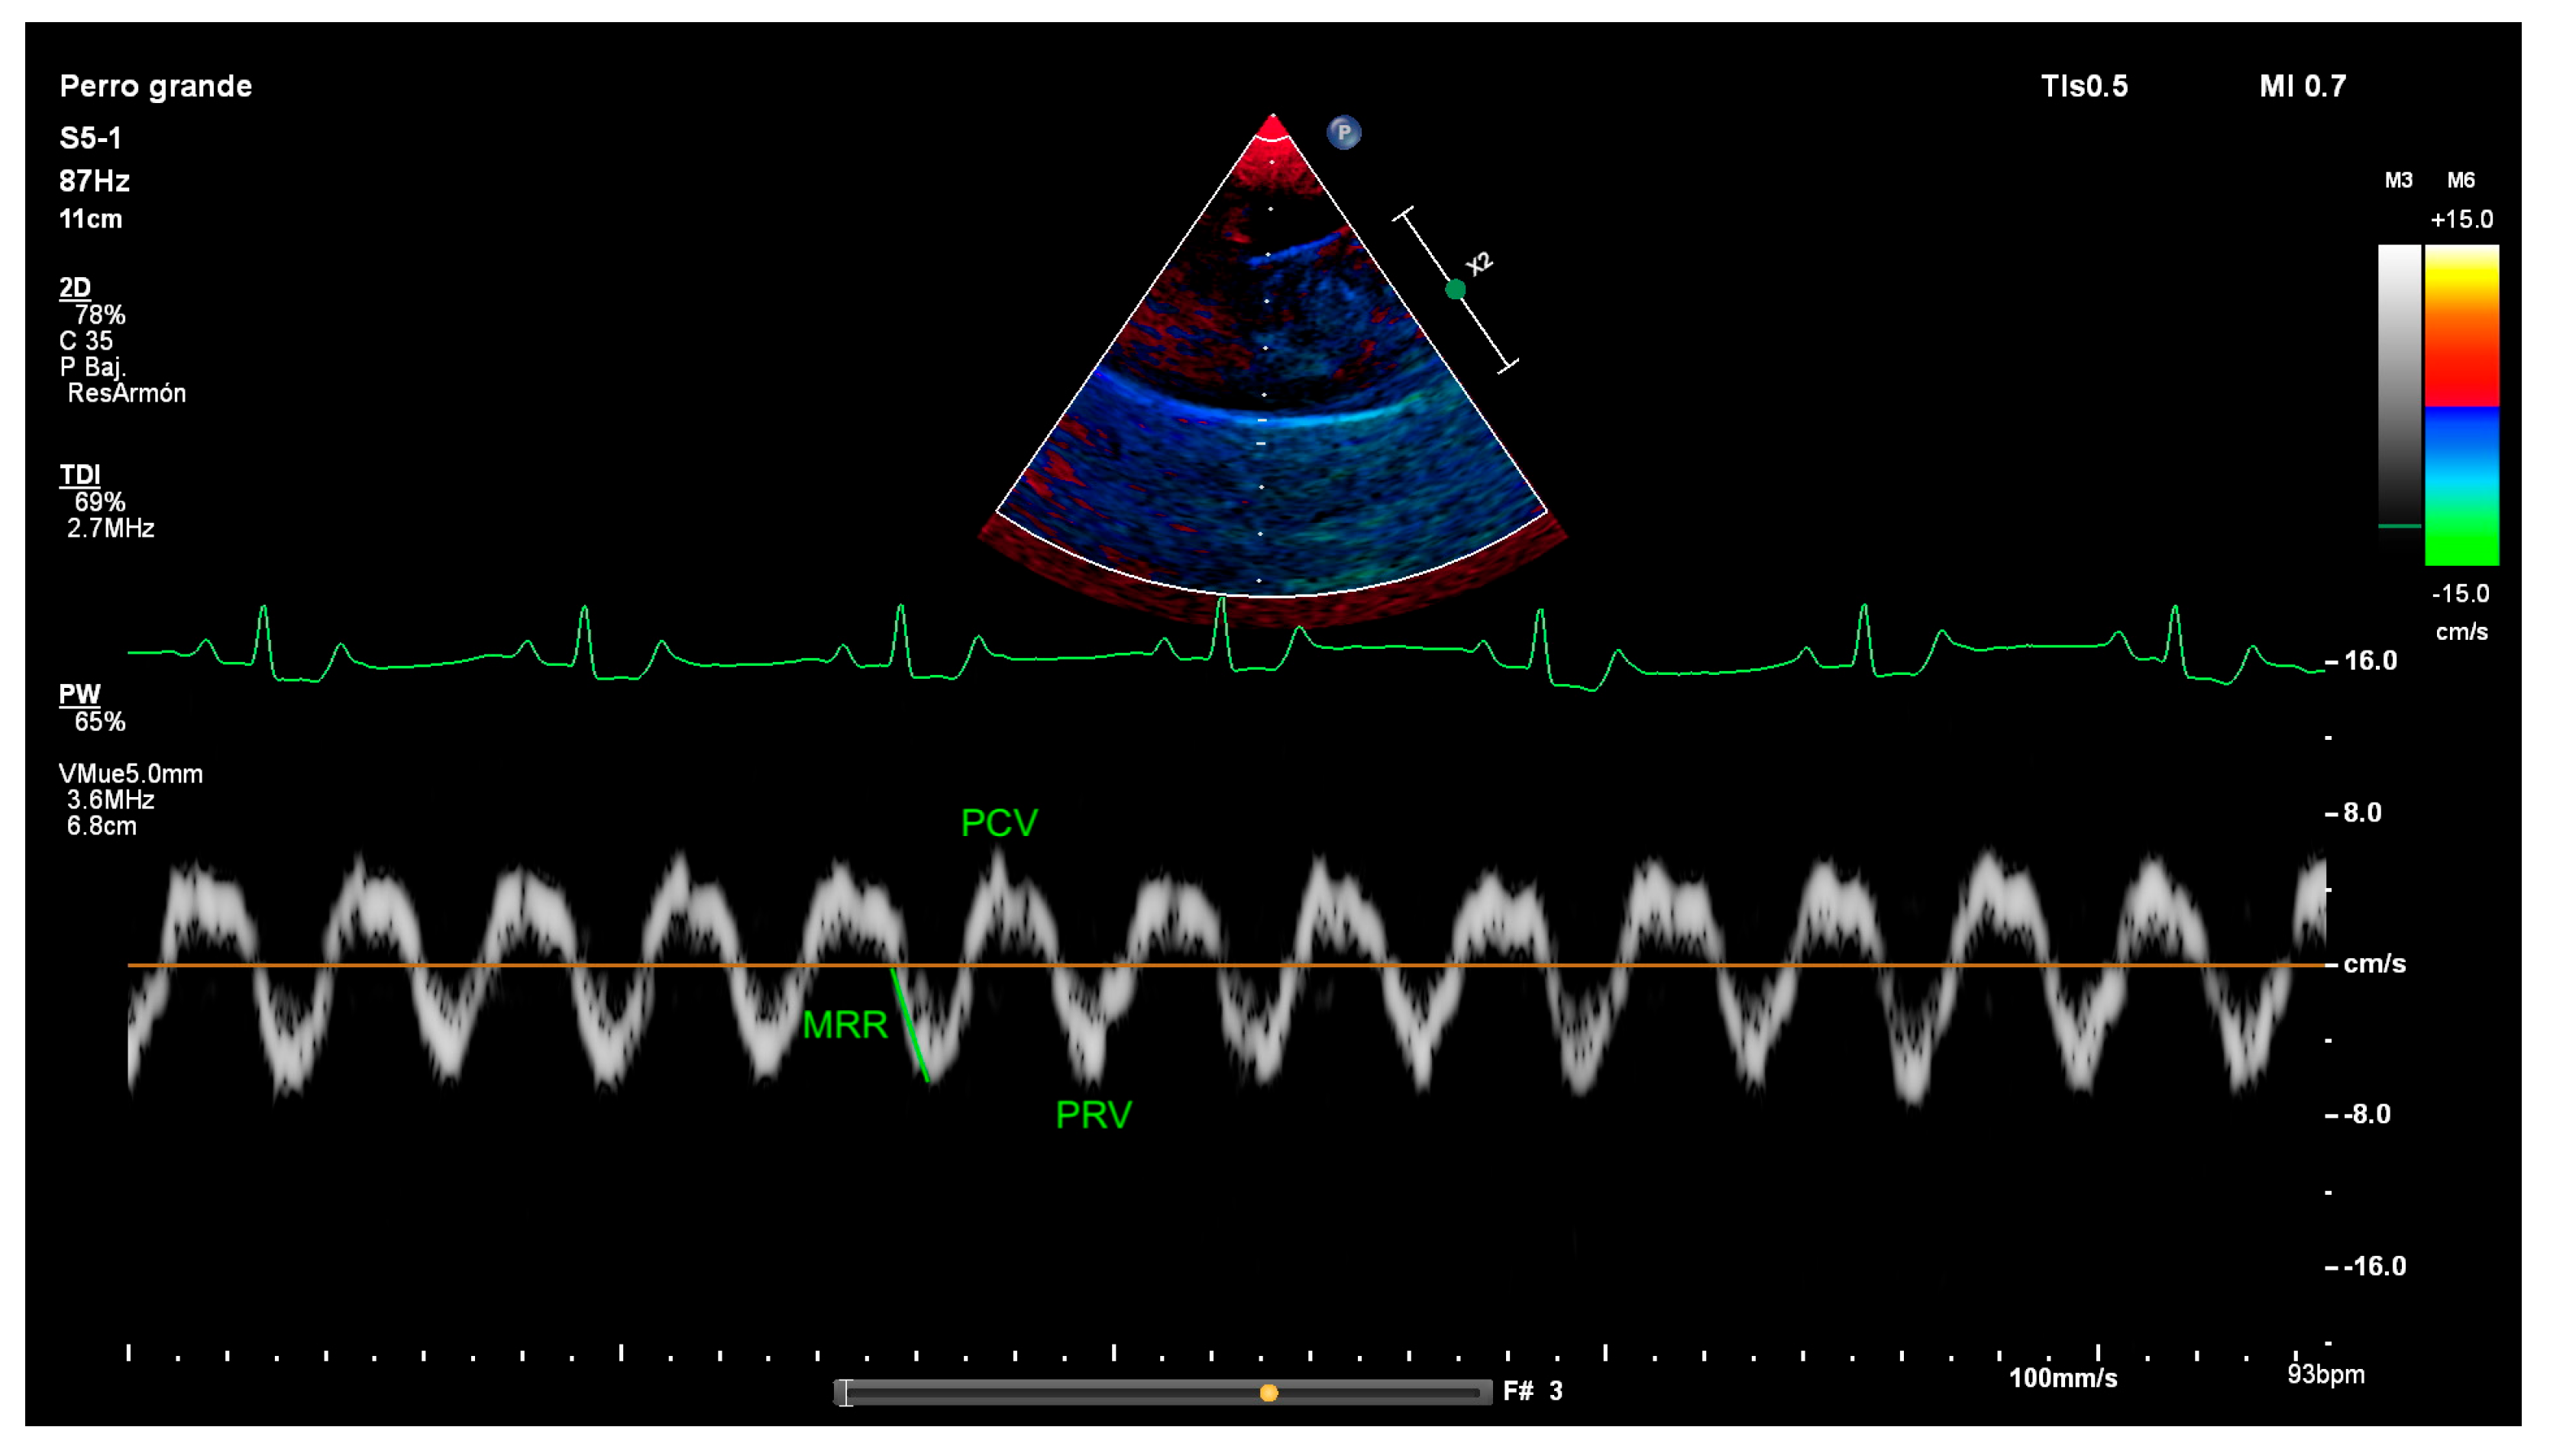

2.2. Diaphragm Ultrasound Technique and Diaphragmatic Measurements

| MRR | Maximal relaxation rate |

| PCV | Peak contraction velocity |

| PRV | Peak relaxation velocity |